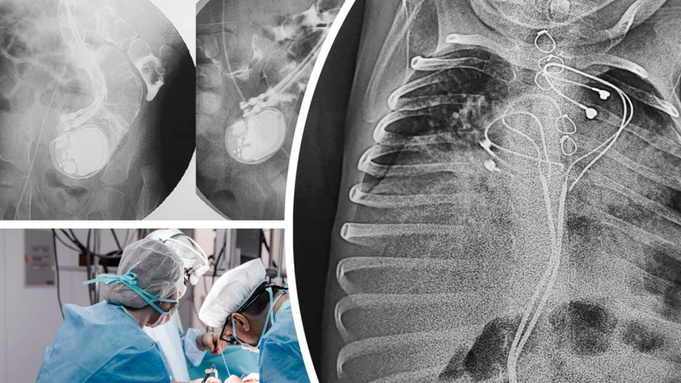

Из-за малого размера тела кардиостимулятор не смогли установить в грудную клетку младенца, поэтому аппарат разместили в верхней части живота, поверх брюшины и прямой мышцы. Электроды прикрепили к правому предсердию и верхушке правого желудочка.

Однако три года спустя мальчика привезли в барнаульскую больницу с высокой температурой и симптомами кишечной непроходимости. В месте имплантации кардиостимулятор прощупать не удалось. Уже на рентгене стало понятно, что аппарат проник в кишечник и оставался там, продолжая работать и задавать ритм сердцу.

"Кардиохирурги Тимур Хапаев и Сергей Иванцов имплантировали однокамерный кардиостимулятор в грудь, а хирурги Владислав Цыганок и Юрий Койнов извлекли устройство, отсекли инфицированные электроды и закрыли дефект кишечной стенки. После курса антибактериальной терапии на десятый день ребенок был выписан в удовлетворительном состоянии", – пояснили в клинике Мешалкина.